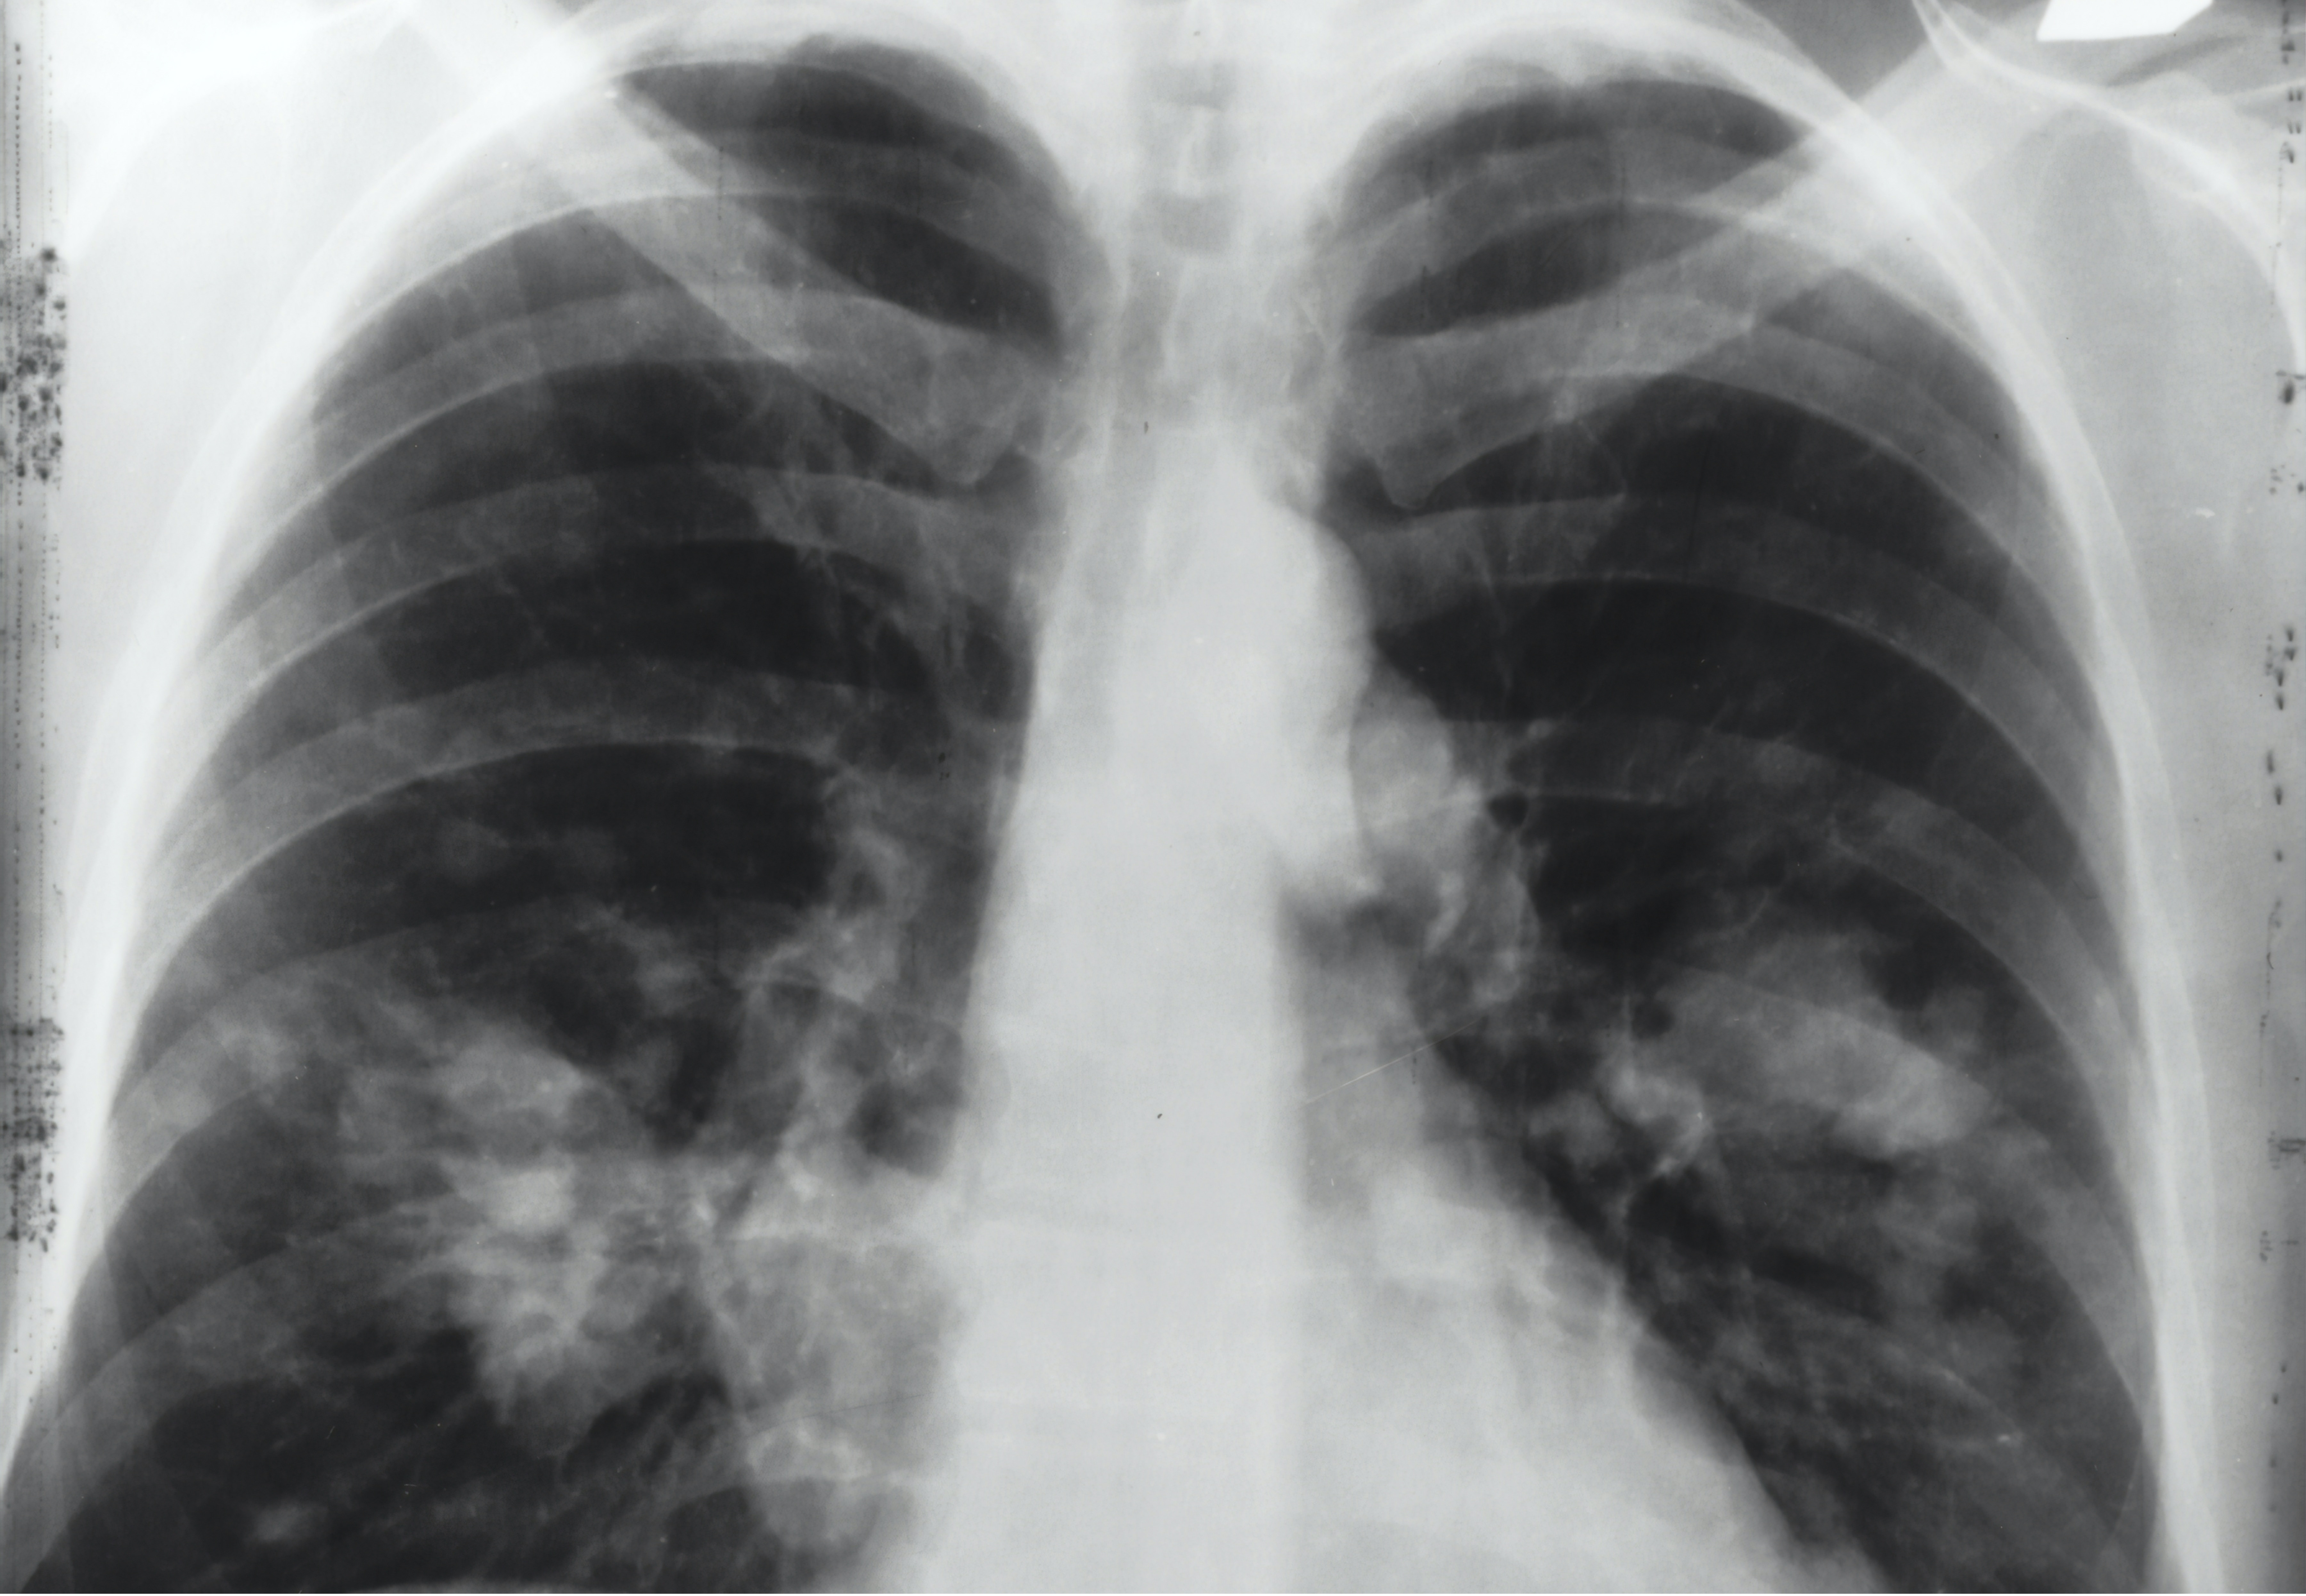

Lung cancer is the leading cause of cancer-related deaths worldwide, but a complete understanding of the biological mechanisms underlying this disease is lacking. Tumours are made up of different types of cancer cell, each with different characteristics; this so-called intratumour heterogeneity can drive tumour evolution and disease progression. The aim of the TRACERx study is to determine the relationship between intratumour heterogeneity and clinical outcomes.

In the lead paper published in Nature, Charles Swanton and colleagues assessed 1,644 tumour regions sampled during surgery or follow-up from 421 patients with non-small cell lung cancer (NSCLC), the most common type of lung cancer. The cohort consisted of patients with stage I, II or III disease who had a range of NSCLC subtypes, including 248 lung adenocarcinomas. The authors identified differences in the genome stability and patterns of intratumour heterogeneity that are associated with patient outcomes.